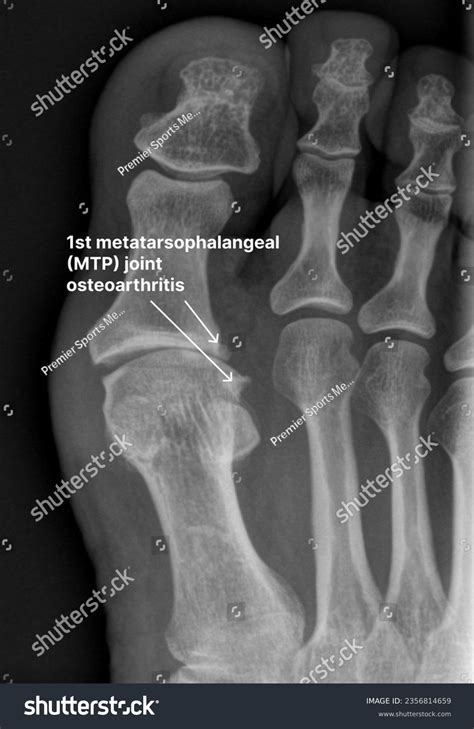

• Hallux Rigidus: This condition is characterized by stiffness and limited range of motion in the 1st MTP joint. It often results from osteoarthritis and can cause significant pain during activities that require pushing off with the big toe.

Diagnosing problems with the 1st MTP joint typically involves a combination of physical examination, medical history, and imaging tests. A healthcare professional will assess the joint's range of motion, tenderness, and any visible deformities. Imaging tests such as X-rays, MRI, or CT scans may be used to get a clearer picture of the joint's structure and identify any underlying issues.

Imaging tests provide detailed views of the joint and surrounding structures. X-rays can show bone abnormalities, while MRI and CT scans offer more detailed images of soft tissues, ligaments, and tendons.

• 1st mtp joint arthritis

• 1st mtp joint osteoarthritis